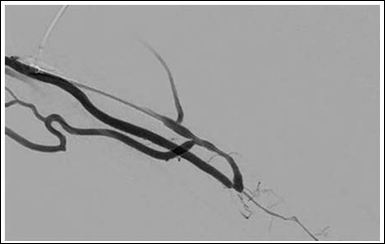

We chose a retrograde access to the cephalic vein. Catheteter angiography confirmed the ultrasound test results (Figure 1). Out flow of the cephalic vein was through basilic vein, cephalic vein of the upper arm and deep venous system in the cubital fossa via drainage through the perforating vein (Figure 2). We performed a balloon angioplasty of the arteriovenous fistula with a plain balloon (4 mm) at the end of the procedure.

Figure 1: Retrograde access to the cephalic vein of the forearm showing the stenosis of the anastomosis and the two draining branches.

Catheter angiography shows vascular anatomy of the fistula with out flow obstruction at the upper arm cephalicvein (Figure 3) and well-developed collaterals (Figures 1 and 4). Troubleshooting was not such as adequate as we did appreciate preexisting problems in this case. Figure 1 demonstrates primary flow is drained through the collateral in the basilic system. Figure 2 shows inadequate drainage into the deep venous system through elbow perforator with lesions in upper arm cephalic vein and non-visualization of median cubital vein.